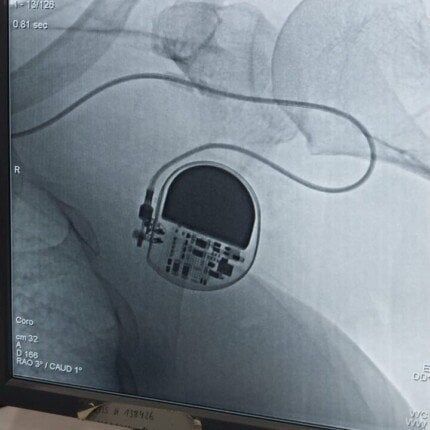

نجح الفريق الطبي بقسم أمراض القلب والأوعية الدموية بمستشفى «قفط التخصصي» بمحافظة قنا، في إجراء عمليتين دقيقتين لزراعة منظم ضربات قلب دائم (Permanent Pacemaker).لسيدتين مسنتين.

الحالة الأولى: سيدة تبلغ من العمر 59 عاماً، كانت تعاني من تباطؤ حاد واضطراب خطير في نظم القلب.

الحالة الثانية: سيدة تبلغ من العمر 67 عاماً، تعاني من هبوط حاد في كفاءة ضربات القلب.

وعقب التشخيص الدقيق تم التعامل بتركيب المنظمات الثابتة، وقد تماثلت المريضتان للشفاء التام وغادرتا المستشفى بحالة صحية مستقرة بفضل الله.